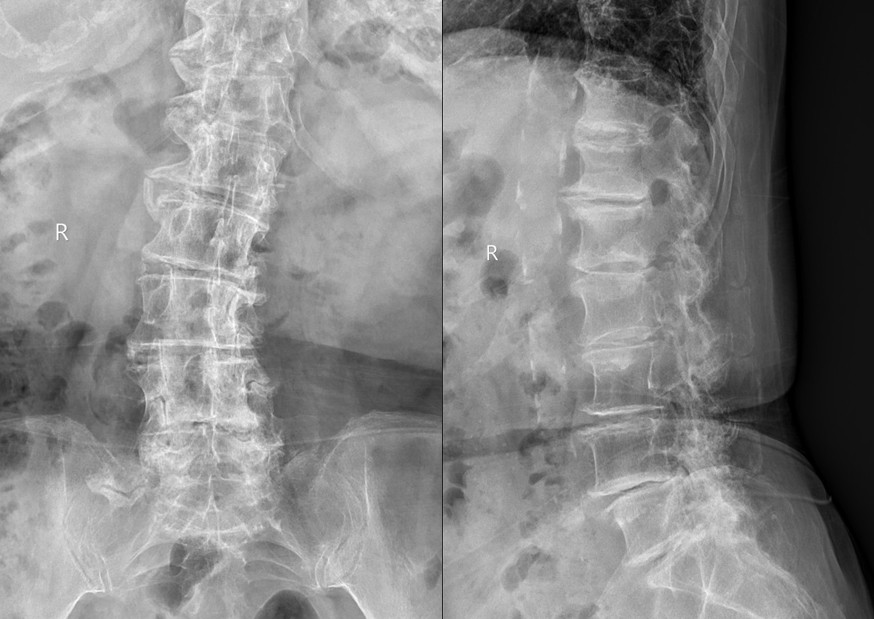

患者郭某某,实际年龄92岁,女性,2月前无明显诱因出现腰痛,双下肢放射痛,逐渐无法行走,症状逐渐加剧,为求进一步诊治,来我院就诊。经柏传毅教授仔细的问诊及查体,结合X线、磁共振等影像学检查,诊断“腰椎滑脱、椎间盘突出合并椎管狭窄,退变性侧凸”。患者入院时腰部疼痛剧烈,双下肢放射痛,无法下地行走,只能卧床,且基础情况病多,既往患有心脏病及糖尿病,长期卧床容易诱发下肢静脉血栓甚至肺动脉栓塞从而危及生命。

患者入院后经过全面的检查和多学科会诊,积极术前准备,柏传毅教授和党晓谦主任、时志斌主任讨论后决定采用全麻脊柱微创通道下为患者行椎间盘髓核摘除,椎管扩大,融合器植入椎弓根固定手术,使患者尽早恢复下地行走及日常活动,减少卧床引起诸多的并发症。11月15日在麻醉科张晓琴教授麻醉后,使用脊柱微创通道完成了髓核摘除椎管减压固定手术,顺利完成。术后5天患者下地活动,疼痛明显减轻,患者逐渐恢复正常生活。